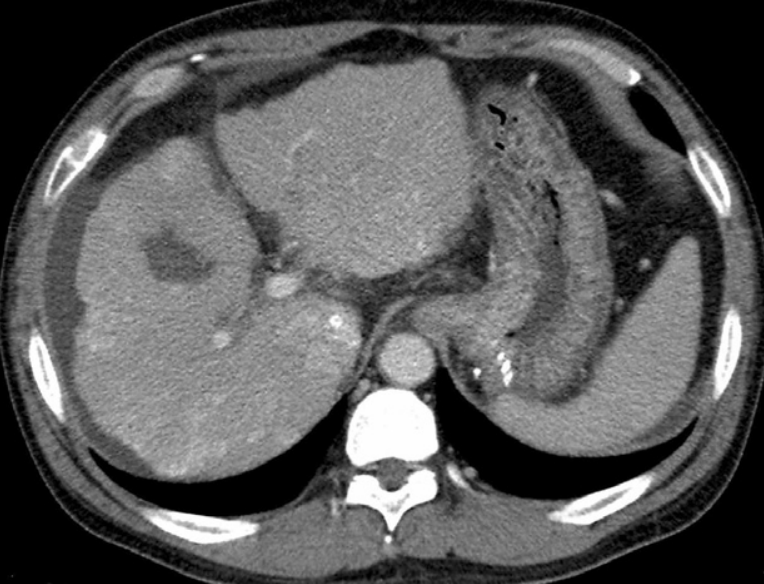

Fig. 7

Follow-up CT scan 16 months after PTO shows no gastric varices.